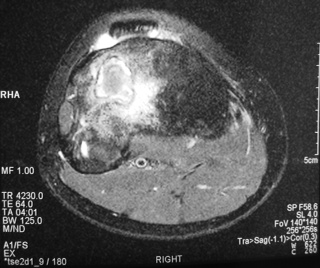

MRI (Fig. 4-7)

• Central low signal intensity with peripheral enhancement on T1-weighted images

• Heterogeneous high signal intensity with low signal in surrounding sclerotic bone on T2-weighted images

Fig. 5

Fig. 4-7: MR imaging of a benign fibrous histiocytoma of the proximal tibia demonstrates a heterogeneous high signal intensity and low signal intensity with surrounding sclerotic bone on T2-weighted images. T1-weighted images show low signal intensity. No soft tissue mass is visible.